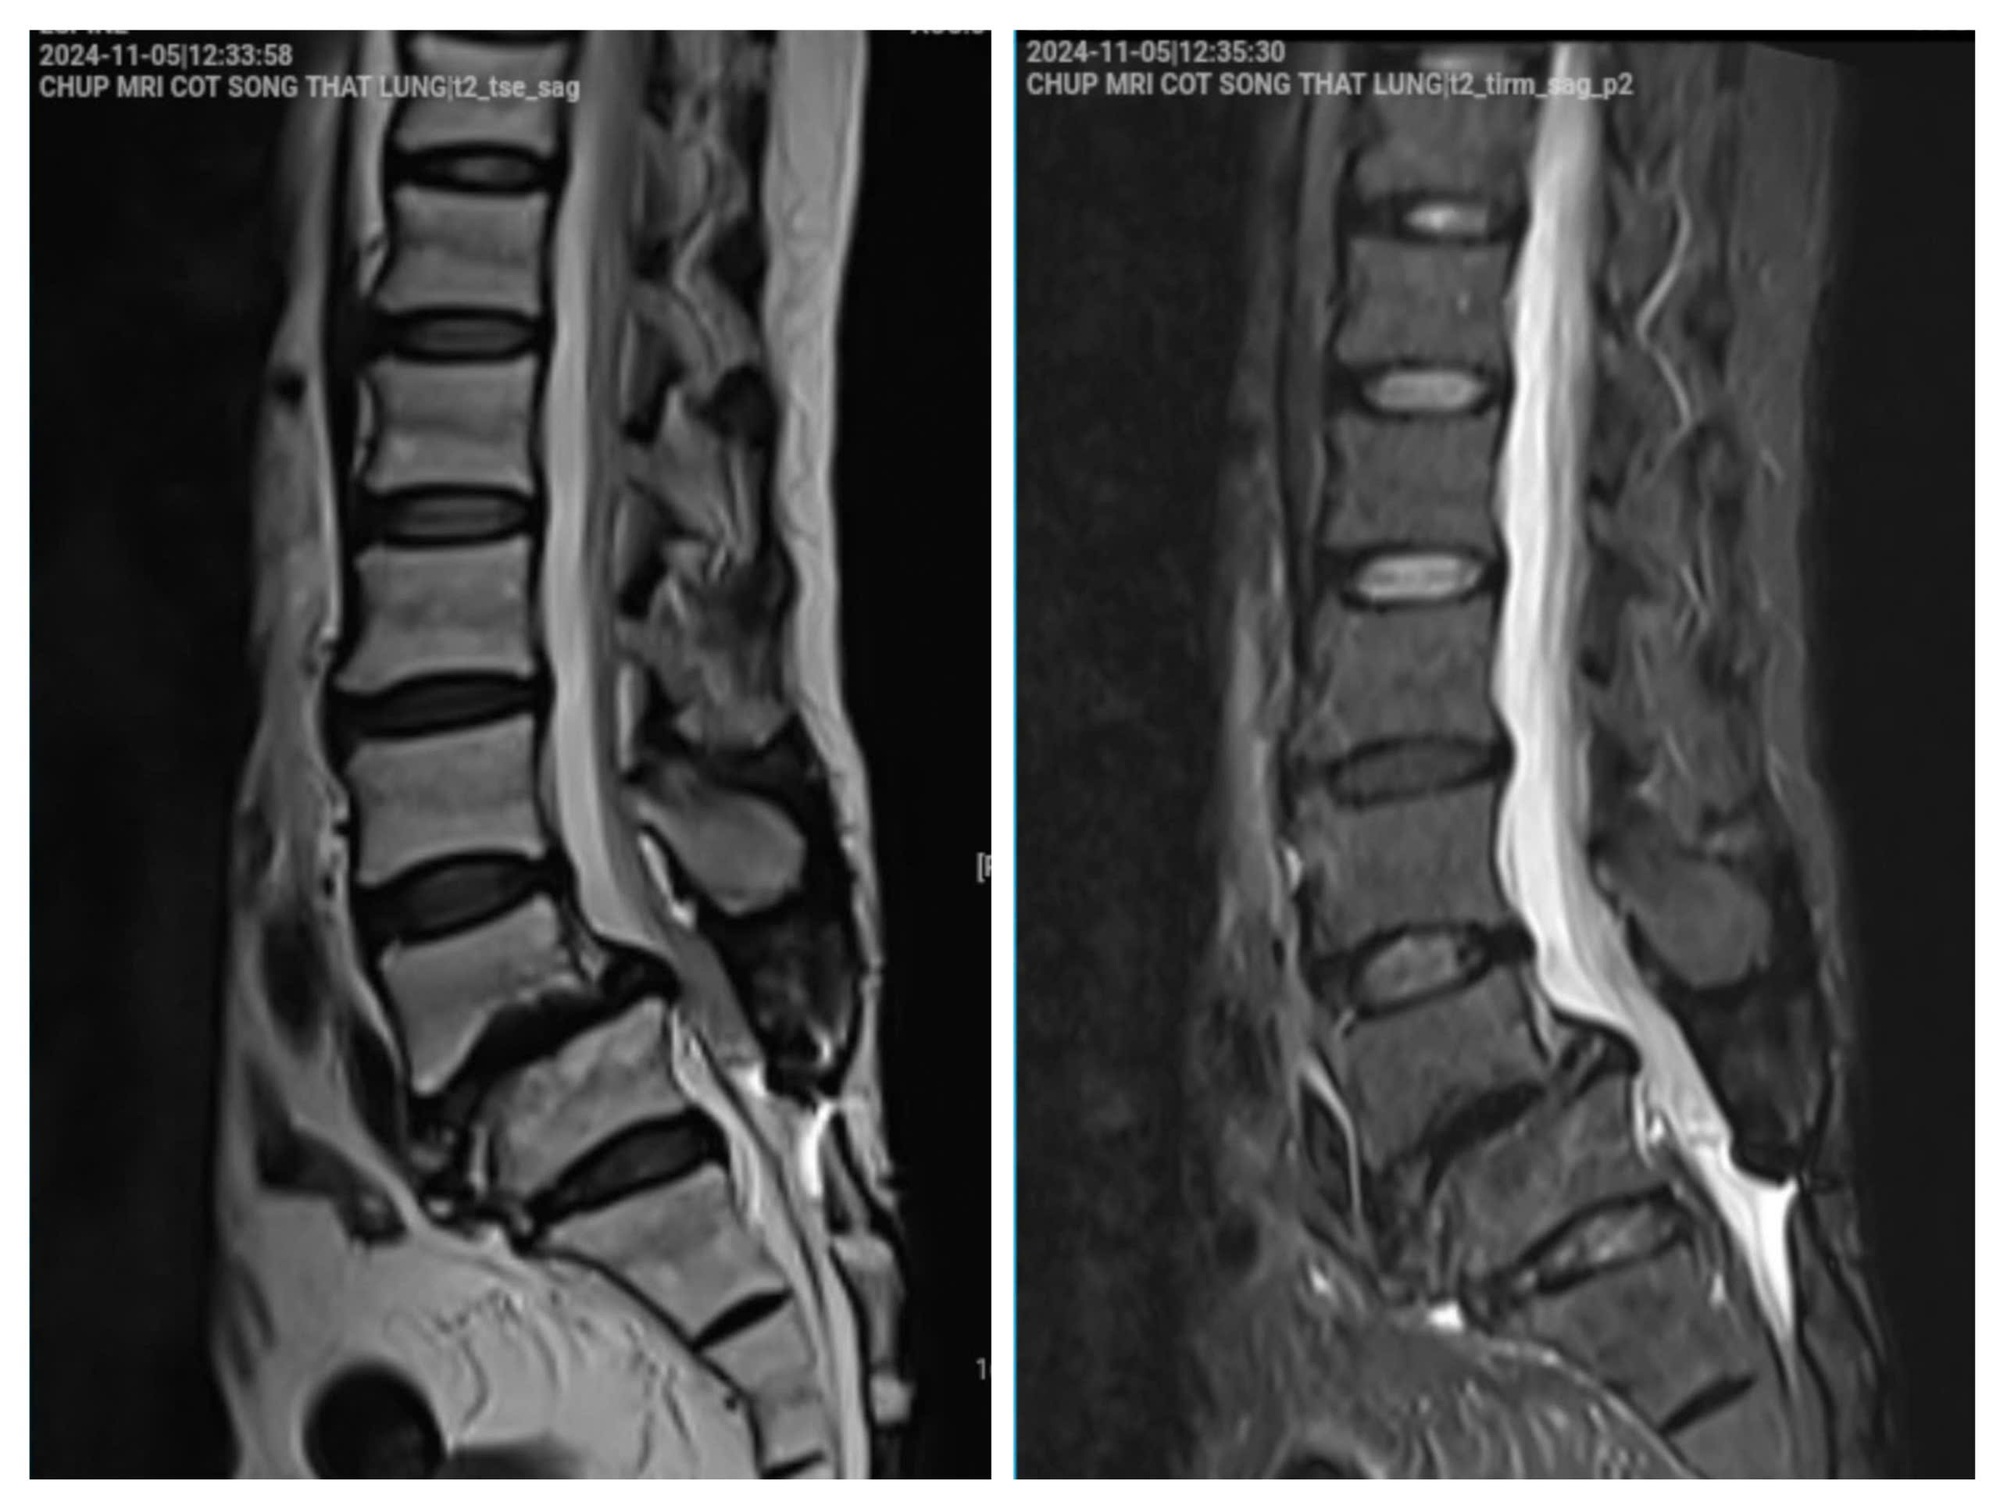

Hình ảnh phim chụp của bệnh nhân vào tháng 11/2024. (Ảnh: BSCC)

Theo BS Cao Thanh Phong, hình ảnh cận lâm sàng cho thấy:

- Hở eo và trượt đốt sống L4 ra trước độ II

- Thoát vị đĩa đệm L4/L5 ra sau, có phần di trú

- Hẹp ống sống nặng, đường kính trước - sau <7mm

- Hẹp ngách bên, lỗ tiếp hợp, chèn ép toàn bộ rễ thần kinh ngang mức L4 và L5

Không dừng lại ở đó, bệnh nhân còn có phình đĩa đệm tại nhiều tầng khác như L2/L3, L3/L4 và L5/S1, gây chèn ép bao màng cứng và hẹp ống sống mức độ nhẹ.